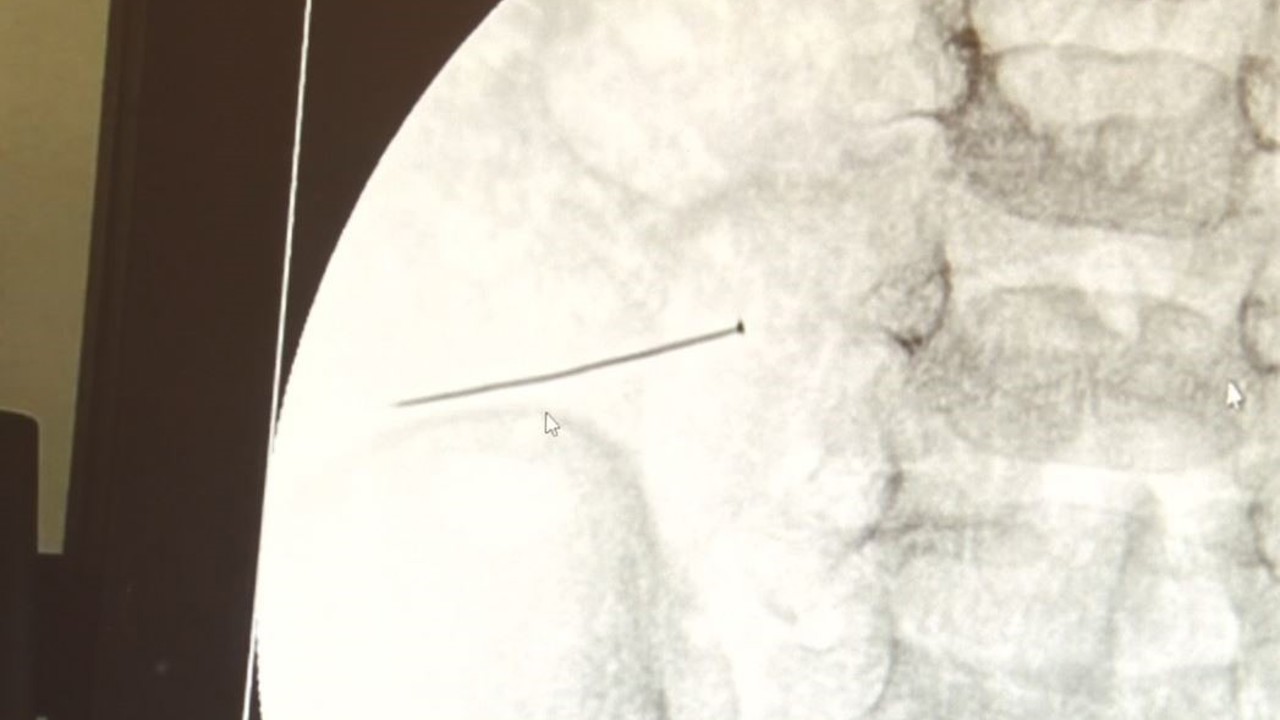

Malatya’da aort yırtığı kapalı yöntemle onarıldı

Malatya Eğitim ve Araştırma Hastanesine yüksekten düşme sonucu getirilen 66 yaşındaki Celal Akbaşlı’nın aort damarında oluşan yırtık, hastanede ilk kez uygulanan endovasküler stent greft yöntemiyle kapalı olarak başarıyla onarıldı.Malatya’da yüksekten düş